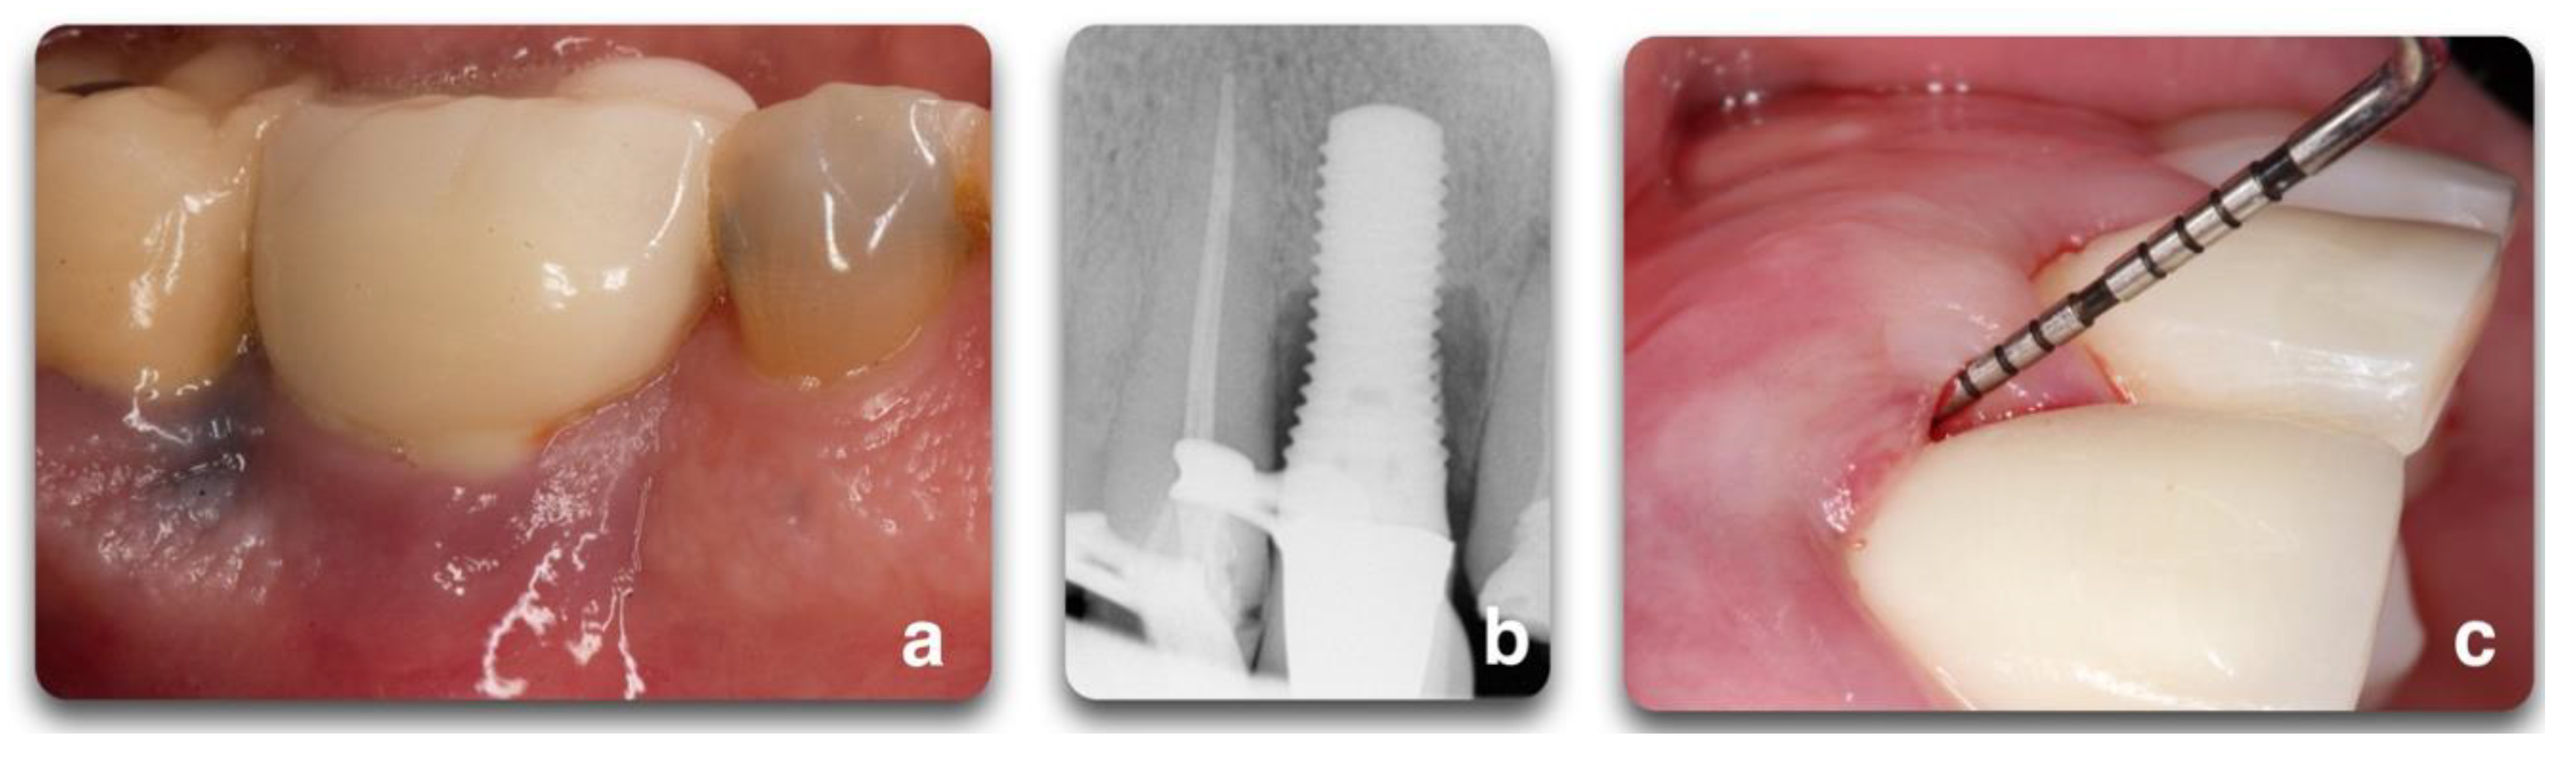

Implant status ranges from clinical health to implant failure and loss. In particular, the implants are classified as health, peri-implant mucositis, and peri-implantitis. The review by Araujo and Lindhe in the 2017 World Workshop [20] described the healthy peri-implant mucosa as comprised of either a keratinized (masticatory mucosa) or non-keratinized epithelium (lining mucosa) with underlying connective tissue. The clinical criteria available to assess and diagnose implant conditions are the same used to assess and diagnose periodontal conditions around teeth: probing depth (PD), bleeding on probing (BOP), suppuration (SUP), and radiographs. These can identify an inflammatory status and periodontal/peri-implant bone loss. The same authors stated that peri-implant health requires the absence of clinical signs of inflammation such as erythema, swelling, and bleeding on probing (BOP). Radiographic evidence of crestal bone changes around implants is important when differentiating peri-implant health from disease. When inflammatory signs appear (BOP, erythema, soft tissue swelling), a diagnosis of peri-implant mucositis (PIM) can be done. When PIM is associated with the progressive loss of supporting peri-implant bone, the diagnosis of peri-implantitis (PI) is established [1]. It is generally accepted that 0.5 to 2 mm of crestal bone loss during healing is considered physiological bone remodeling following implant installation and initial loading [21]. However, any additional radiographic evidence of bone loss more than 2mm after the placement of the prosthetic supra-structure, would suggest PI [21]. Although the conversion from an inflammatory process identified as PIM to PI is not well understood, it is generally agreed that both diseases share the same infectious etiology through the development of biofilm [1]. If the lesion is left untreated, the inflammatory process can lead to progressive peri-implant bone loss and implant failure. In case of an absence of documentation from the time of implant placement to the time of disease manifestation, radiographic bone level ≥ 3 mm in combination with BOP and PD ≥ 6 mm is indicative of peri-implantitis [21] (Figure 1).

Figure 1.

Representation of peri-implant clinical parameters that, associated, can lead to a diagnosis of peri-implantitis. In the sequence above, BOP/Suppuration (a), radiographic bone level ≥ 3 mm (b) in combination with PD ≥ 6 mm (c).